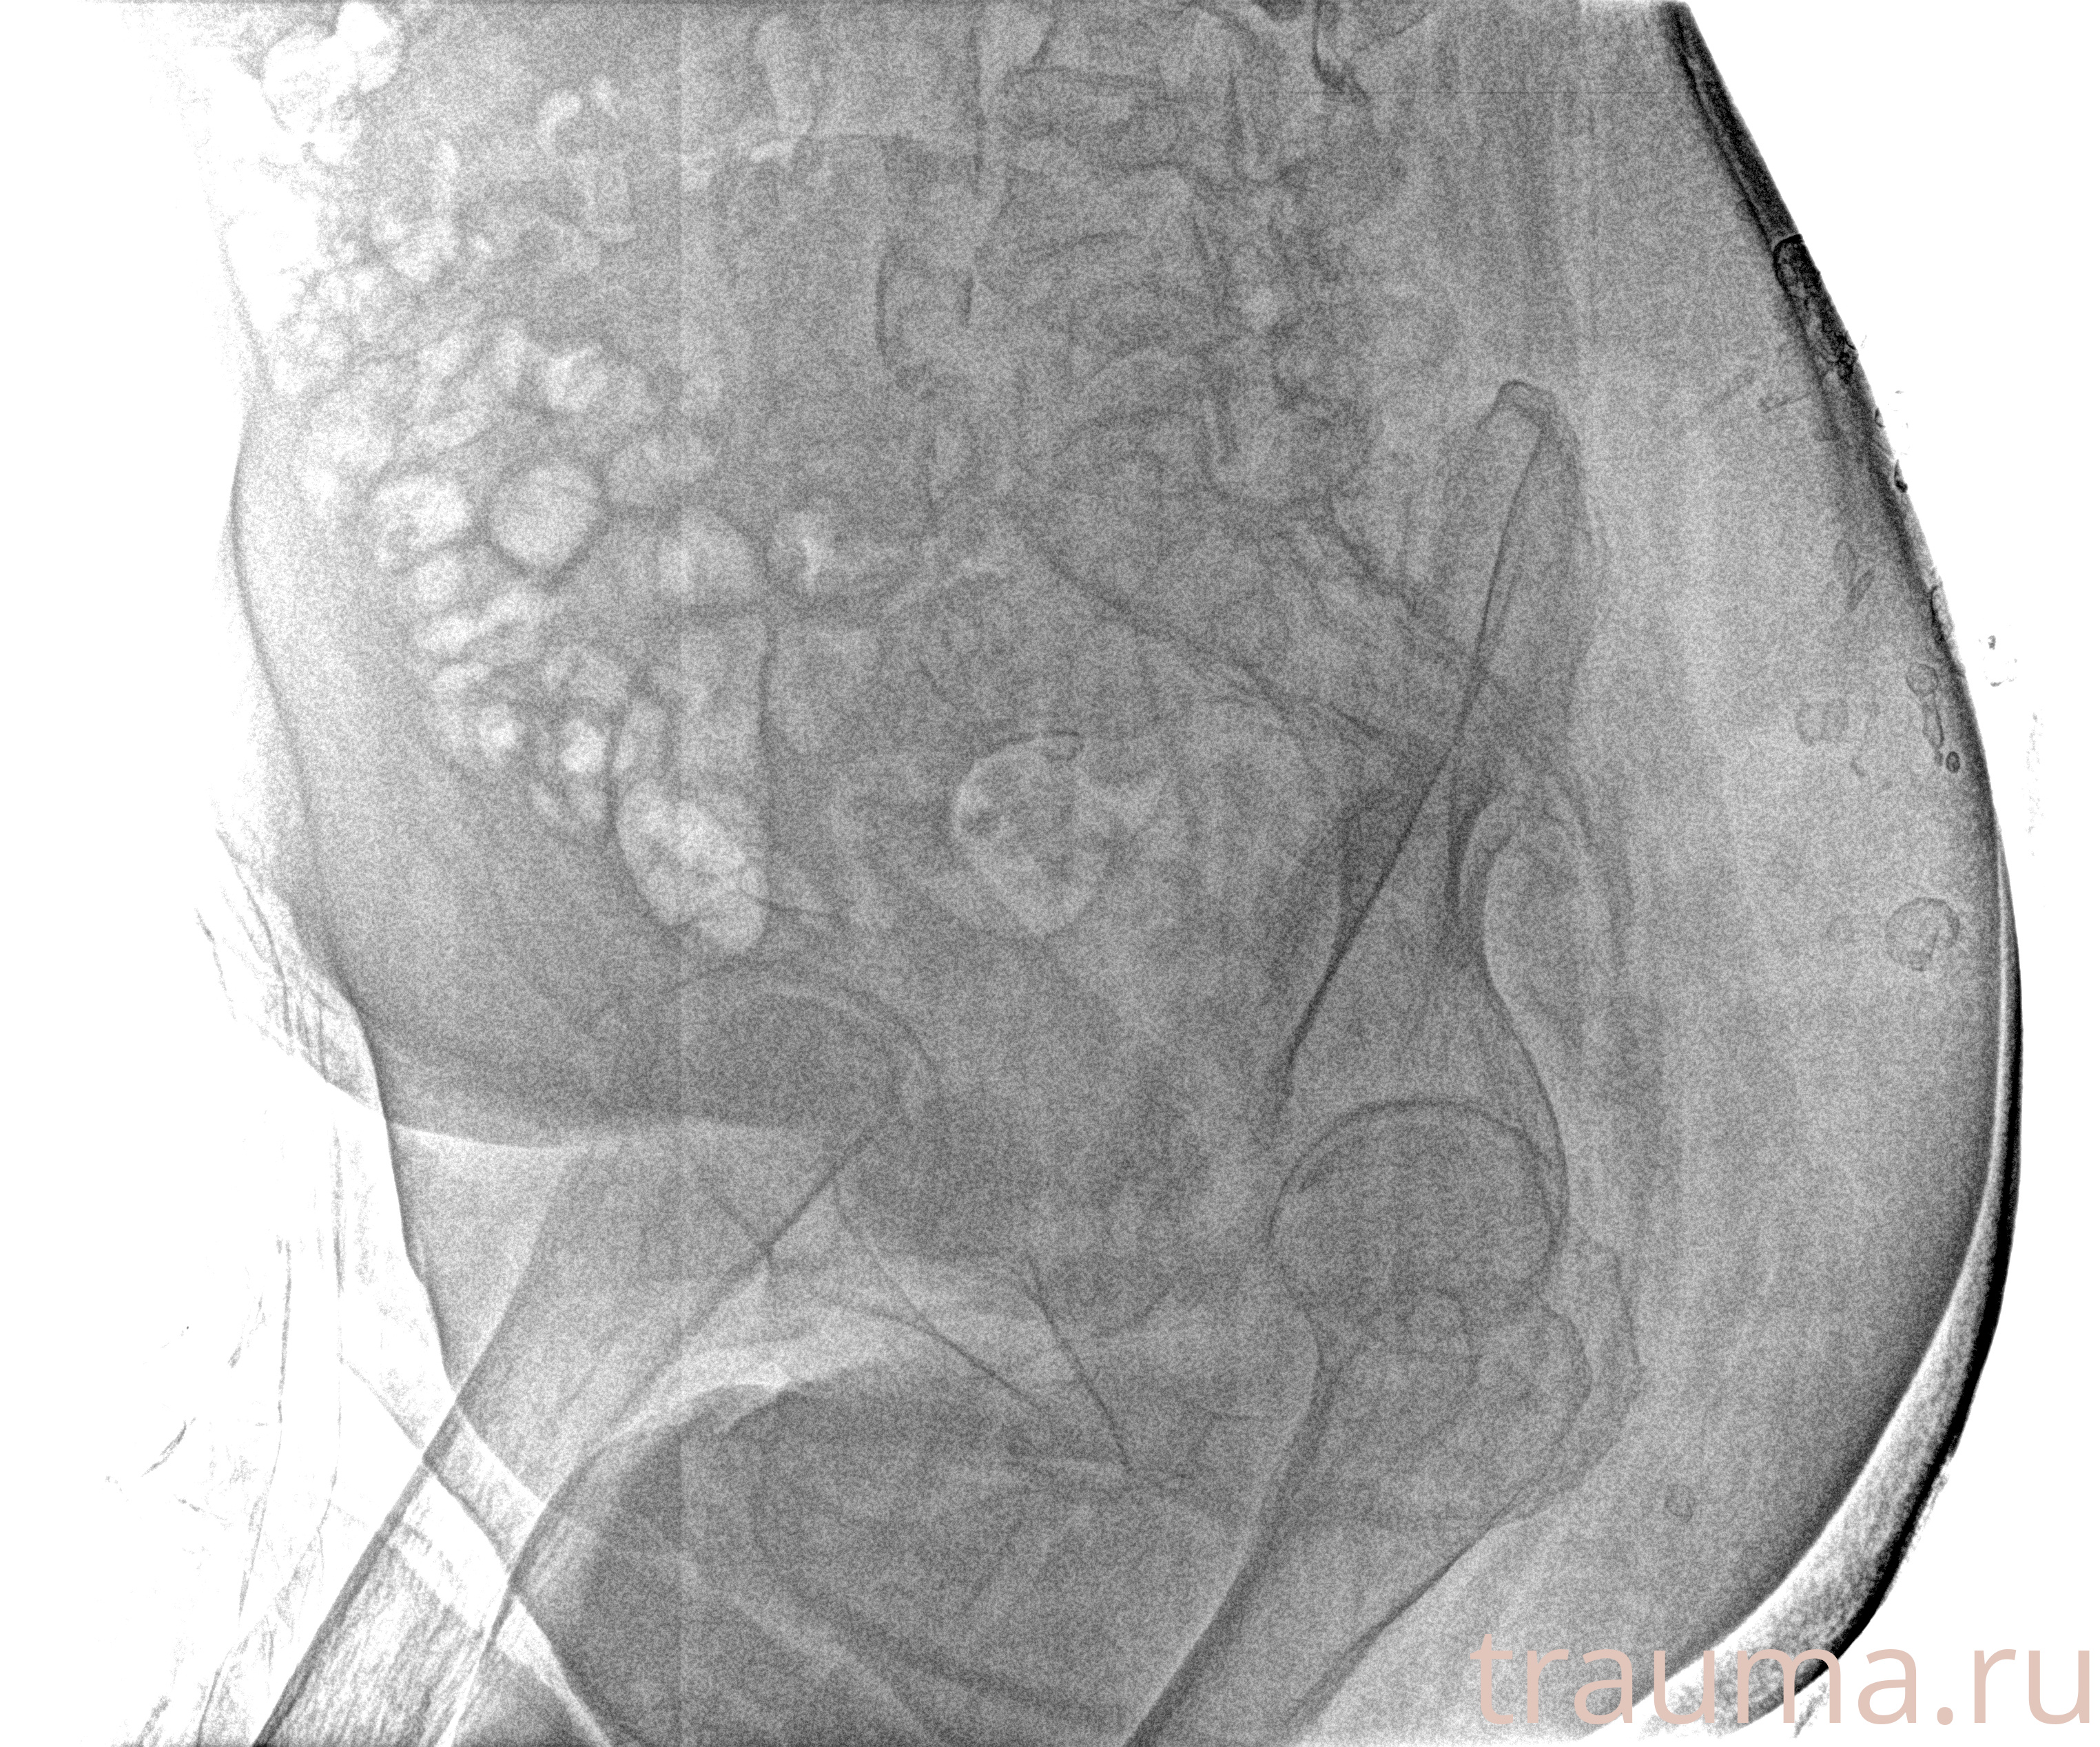

Рентген на дому: по вашему адресу приезжает врач-рентгенолог, травматолог-ортопед с мобильным рентгеновским аппаратом, проводит диагностику травмы или заболевания, делает необходимые рентгенограммы, дает рекомендации по дальнейшему лечению. Получить качественные снимки в домашних условиях возможно благодаря уникальной методике, разработанной МосРентген Центром для института  Склифосовского